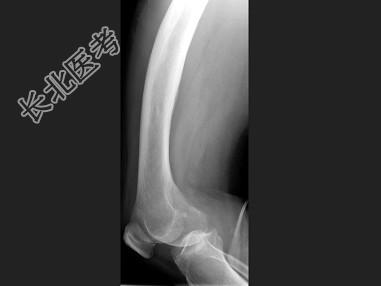

单项选择题男,67岁, 右侧股骨痛,结合图像, 最可能的诊断是 ( )

A、骨纤维结构不良

B、维生素D缺乏病

C、成骨不全

D、软骨发育不全

E、畸形性骨炎